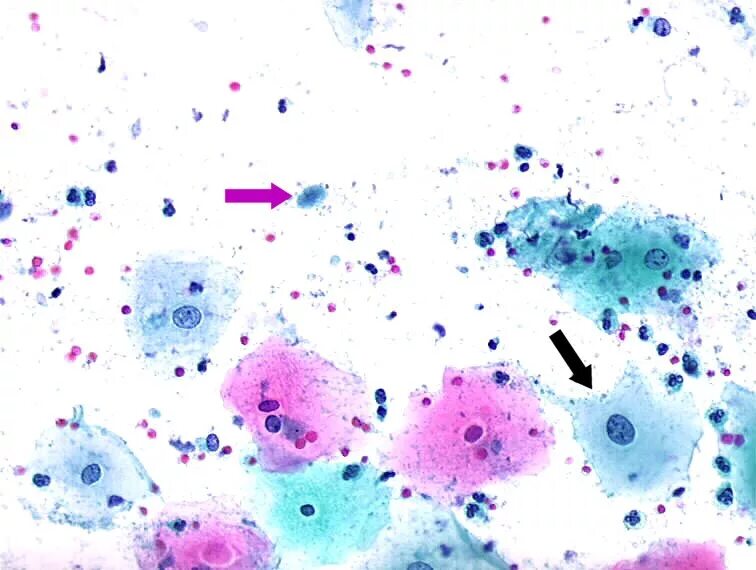

Микроскопия окрашенных